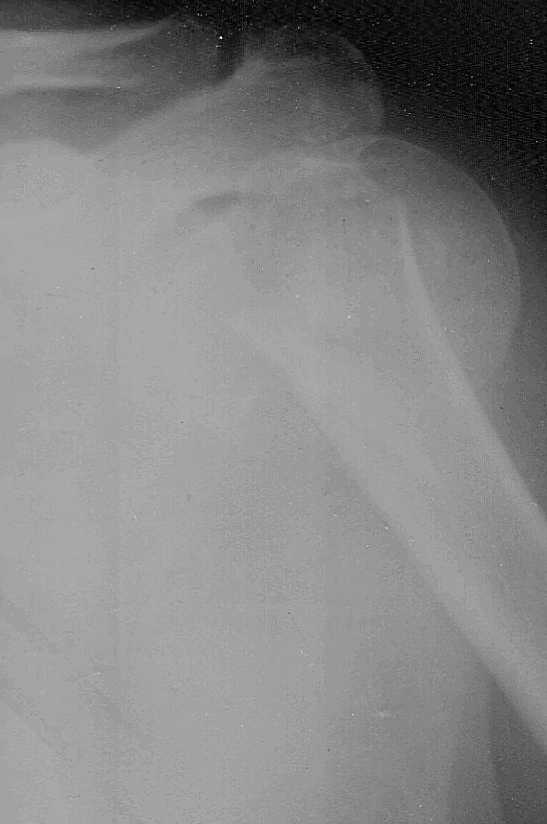

Доброго времени суток,коллеги.Больная 51 год травма 2,11,09 в 20:00

сосудистых,неврологических расстройств нет

3,11,09 выполнена попытка закрытой репозиции,безуспешно. Планируем накостный синтез

Т-образной пластиной.Буду крайне признателен за дельные советы.